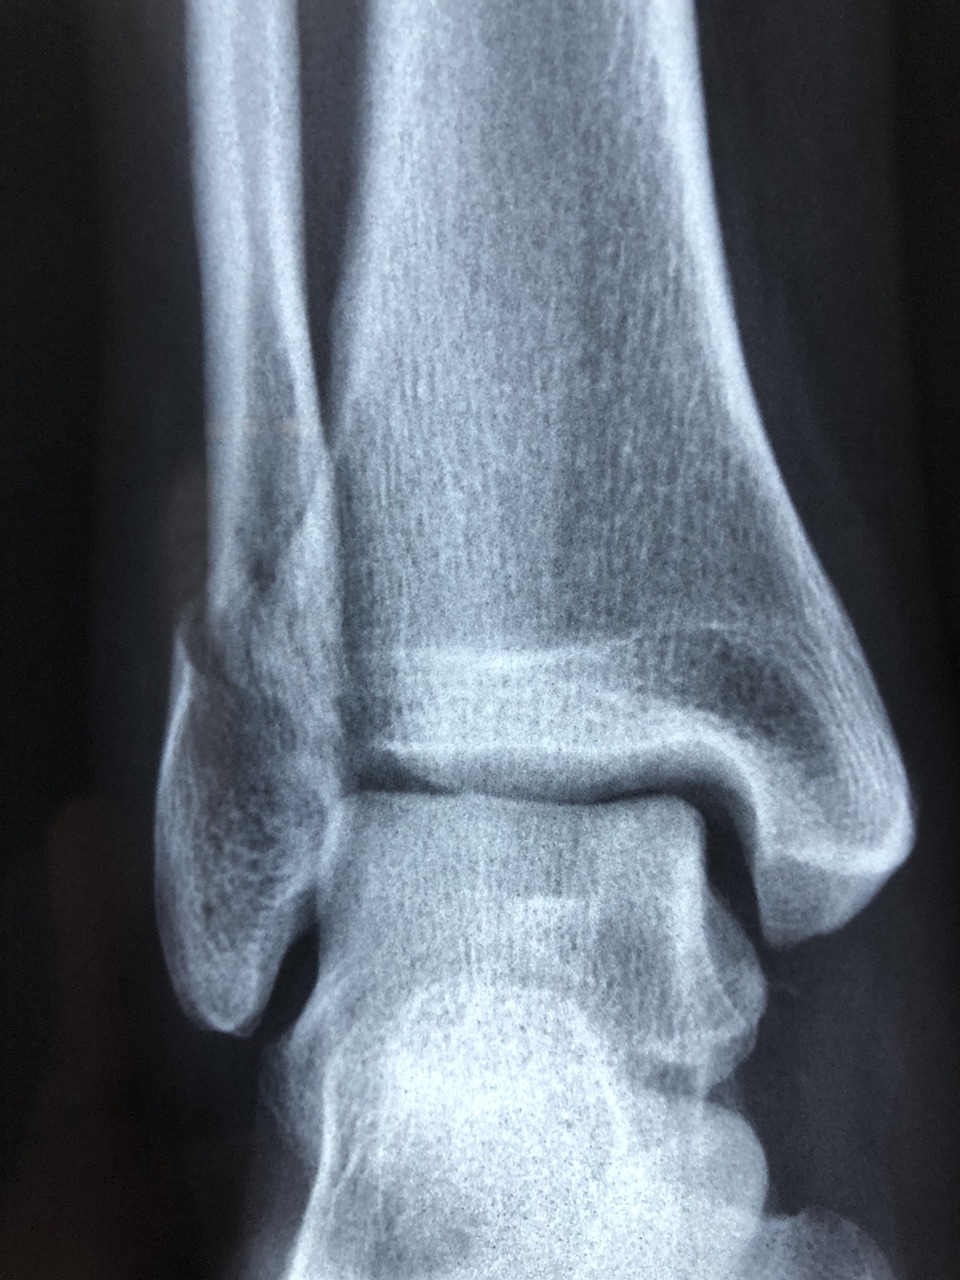

The U.S. Food and Drug Administration (FDA) approved the Patient Specific Talus Spacer 3D-printed talus implant for humanitarian use. The Patient Specific Talus Spacer is the first-in-the-world and first-of-its-kind implant to replace the talus – the bone in the ankle joint that connects the leg and the foot, according to a news release from the agency.

AVN is often caused by a sudden injury – such as a broken bone or a dislocated joint – or sustained damage to the tissue that develops over time, and it occurs when there is a lack of blood supply to bone tissue, causing it to become necrotic, meaning it dies. When the bones of a joint are affected, such as in the case of the ankle, the cartilage that keeps the bones from rubbing together can deteriorate, causing arthritis and pain. Late-stage AVN of the ankle may result in the talus bone partially or fully collapsing. Current available treatments include fusing the joints in the foot and ankle together—a procedure which helps to alleviate pain caused by AVN but eliminates motion in the joint—or below-the-knee amputation.

The Patient Specific Talus Spacer is a 3D printed implant that can be used in talus replacement surgery. The talus spacer is made for each patient individually, modeled from computed tomography (CT) imaging, and is fitted to a patient’s specific anatomy. During the replacement surgery, the patient’s talus bone is removed and replaced with the implant, which is made from cobalt chromium alloy.